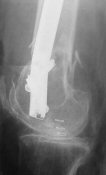

THX, initial images are

1,

2.

At that moment we had in stock only the 10 mm solid nails so of course there was no idea about early weight bearing. But it was quite enough for early knee ROM excersises (see attached). Two locking screws through the distal block provided that.